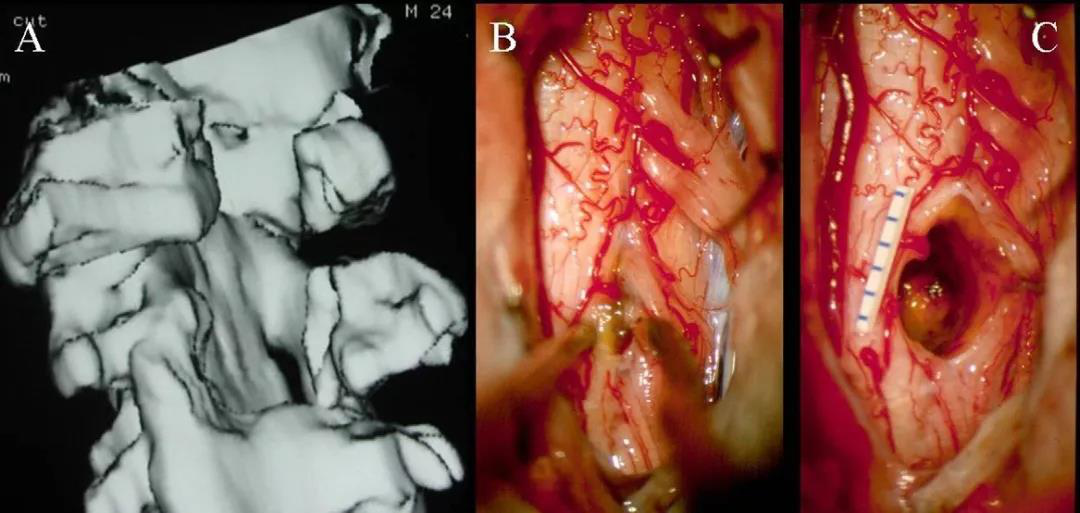

(A-C)3D-CT掃描顯示位于C1-2水平的髓內(nèi)CM的術(shù)后圖像。(B)在術(shù)中脊髓表面觀察到含鐵血黃素染色。(C)完全切除髓內(nèi)CM,顯示髓鞘切開的程度。